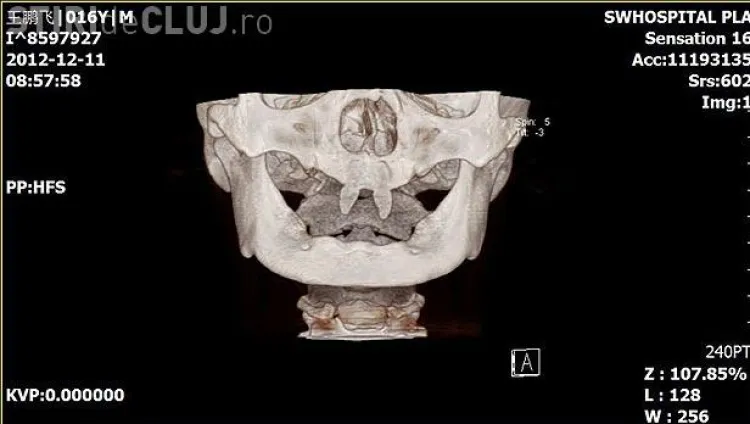

Un băiat din China i-a uimit pe medici, după ce i-au crescut doi canini foarte ascuţiţi, neavând alţi dinţi în gură.

Wang Hui, mama lui Wang Pengfei, și-a dus băiatul la un spital local din Chongqing (sud-vestul Chinei), pentru a vedea ce se întâmplă.

Medicii i-au spus că cei doi canini vor fi operați când va fi un adult și că totul va costa 10.000 de euro. ”Nu are prieteni şi își dă din ce în ce mai mult seama cât de diferit este faţă de ceilalţi copii”, a spus mama copilului, care a adăugat că fiul ei a devenit mai izolat şi agresiv cu colegii, conform rtv.net.